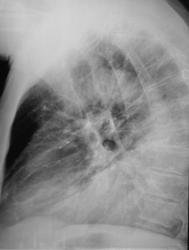

Я еще вижу тень в верхушке правого легкого, и в левой верхушке. Еще мне кажется, что в 6 сегменте несколько теней (на боковом снимке). Тубанамнез какой?

Рискну предположить, что основная тень в задне-базальном отделе - гидроторакс. Но и снижение прозрачности легочной ткани есть, не могу локализовать, то ли языки, то ли восьмерка. Узи плевральных (заодно и легочная ткань видна будет) ну, или томография (кто к чему привык, у кого что под рукой), + динамика.

Левосторонняя нижнедолевая пневмония. лечение. динамика.

Как бы эта нижнедолевая пневмония не оказалась уже ателектазом. А почему "пневмоторакс"? Внезапные боли?

Как-то не похоже на инфильтрацию, я бы думала о гиповентиляции нижней доли и центральном образовании

Данных за пневмоторакс нет.Левосторонняя нижнедолевая пневмония(предварительно).Верхнюю долю уточнять на контроле.

А треугольная тень в верхней доле на боково м? Ателектаз S3? И округлая тень в верхушке на прямом снимке слева! еденичный мтс или специфическое?

Прошу прощения!!))) тень округлая справа в верхужке!! её как расцениваете?

Плотная очаговая тень, оценка после томографии (или с рентгенархивом). В отношении мягких тканей - мнение то же, что в предыдущем 21 посте.